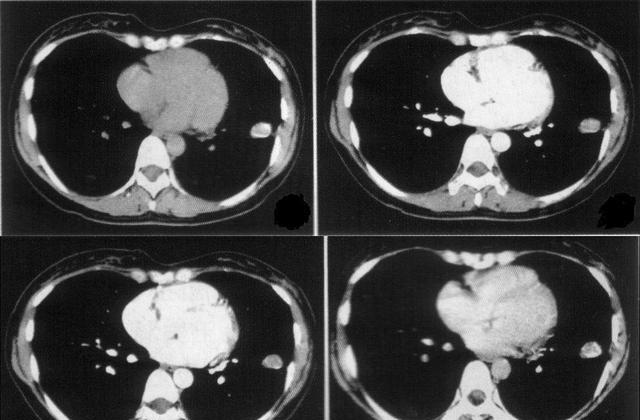

年龄越来越大,藏大叔的肺也逐渐出现 问题 ,刚开始还不在意,直到忍不了才和儿子说,在儿子的坚持下去看了医生,做了全身体检。没想到这一体检还真出毛病了,竟然患了肺结核,肺也有轻微的 炎症 。

医生说,幸好发现得早,否则后果不堪假想,很有可能会 危及生命 。